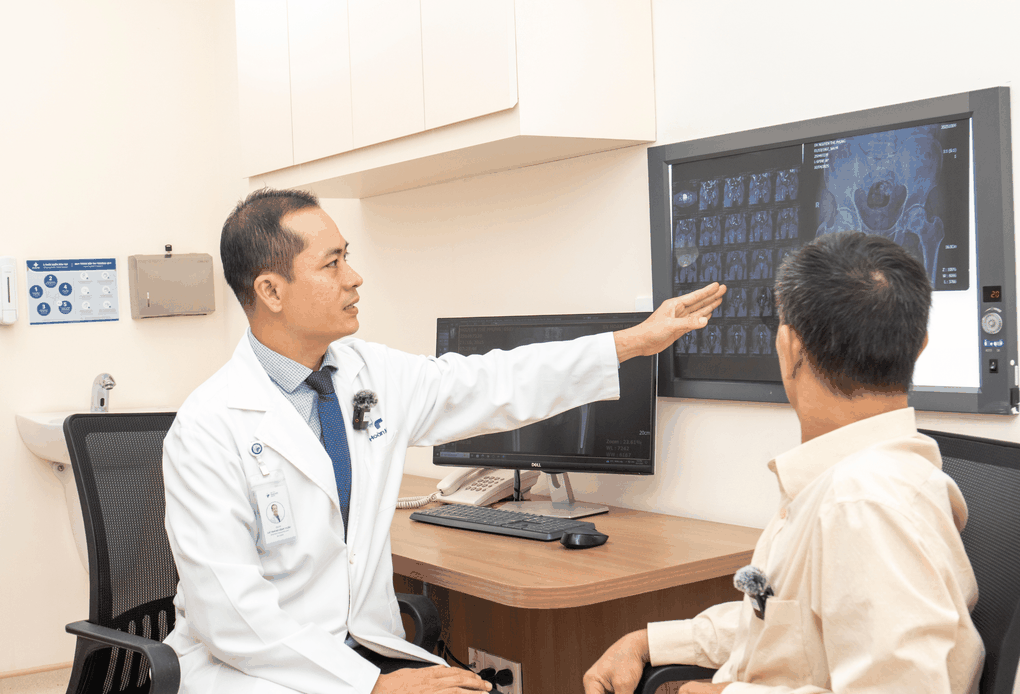

Bác sĩ đánh giá hình ảnh X-quang và phân tích mức độ tổn thương khớp (Ảnh: BVCC).

Sau khi thăm khám và đánh giá hình ảnh cận lâm sàng như X-quang, MRI, BS.CKII. Hồ Trương Đăng Triều, khoa Chấn thương chỉnh hình, Bệnh viện Hoàn Mỹ Sài Gòn nhận định tình trạng khớp háng bên trái của người bệnh đã tiến triển đến giai đoạn nặng không còn khả năng giữ lại, ảnh hưởng nghiêm trọng đến cấu trúc và chức năng của khớp.